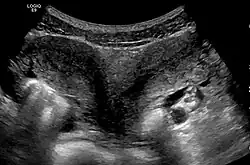

Diagnose

Die Diagnose wird in der Regel durch Sonografie gestellt.